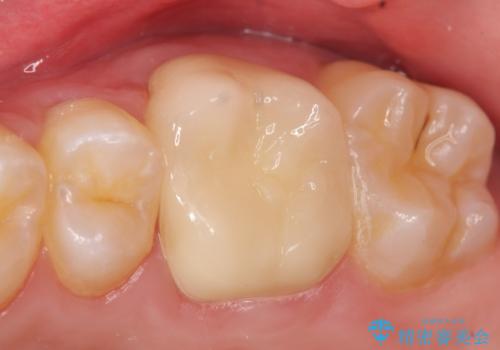

検査の結果左上6に持続痛を認めたため根管治療を行い、症状の緩解を確認後オールセラミッククラウンによる補綴を行いました。

今回用いたオールセラミッククラウンはジルコニアフレームという白い素材の上にセラミックを盛っているため、審美性が非常に高いのが特徴です。

また、ジルコニアは人工ダイヤモンドの材料にも使われているほど高い強度を持っており、そのためオールセラミッククラウンは審美性だけでなく、奥歯やブリッジの補綴も可能とするクラウンです。